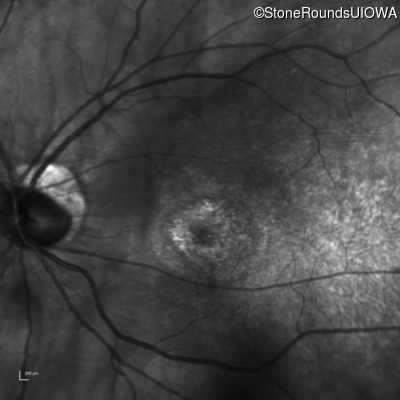

Infrared Fundus Photograph - Right - 20/32 +1

Exemplar

Infrared Fundus Photograph - Left - 20/32 -1